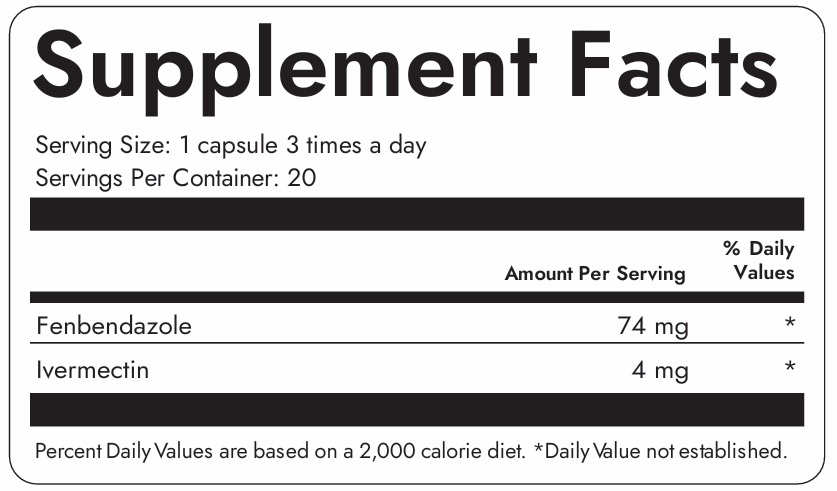

Take 1 capsule 3 times daily with meals. For best results, maintain consistent timing and follow the recommended dosage. Consult with your healthcare provider before starting any new supplement regimen.

Clinically trusted for decades, Ivermectin helps bind and flush out parasites, biofilm waste, and immune disruptors hiding deep in tissues. Our formula uses only the purest medical-grade Ivermectin—no fillers, no toxins.

Fenbendazole is a well-researched anti-parasitic compound known for its powerful detox and cellular repair support. Backed by emerging science, it’s used for everything from gut resilience to systemic cleanup.